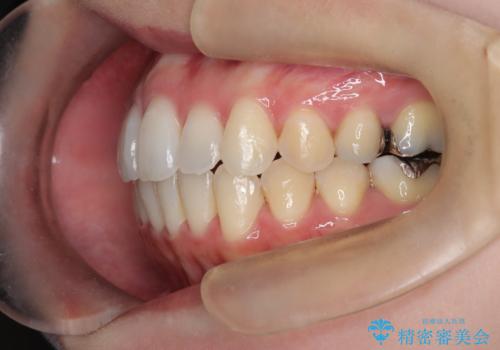

- 前歯のガタガタを主訴に来院された患者様です。

前歯の傾きも少し内側に入るように計画をたて、インビザラインにて治療を行いました。

このぐらいのガタガタであれば、インビザラインで簡単に治すことができます。